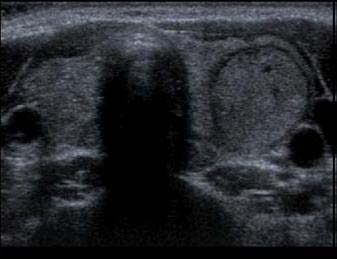

Ultraschall - regressiv-cystischer Knoten ohne Krebsverdacht

Liegt ein kalter Knoten vor, so muss abgeklärt werden, ob es sich um einen "harmlosen" Knoten handelt oder ob Verdacht auf Schilddrüsenkrebs besteht. Neben der Szintigraphie ist heute primär der Ultraschall (Sonographie) die wichtigste Untersuchung zur Abklärung und Einschätzung von Knoten. "Echoreiche" und gut abgrenzbare Knoten deuten auf gutartigen Charakter hin harte, echoarme und schlecht abgrenzbare Adenome sind eher kritische Zeichen ebenso Knoten mit Mikrokalk, vor allem, wenn dasselbe Ultraschallmuster auch in Lymphknoten vorliegt. Metastasen in Lymphknoten zeigen häufig dasselbe Gewebebild.